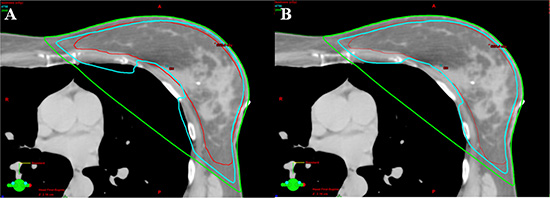

Figure 1: Comparison of isodose line of lung V20Gy (green line). (A) The coverages of 95% isodose line (cyan) for PTV (red) were similar between techniques. More lung volume involved in the isodose line of 20 Gy in 3DCRT plan from one patient. (B) Comparing to 3DCRT, less lung volume involved in the isodose line of 20 Gy in eComp plan for the same patient.